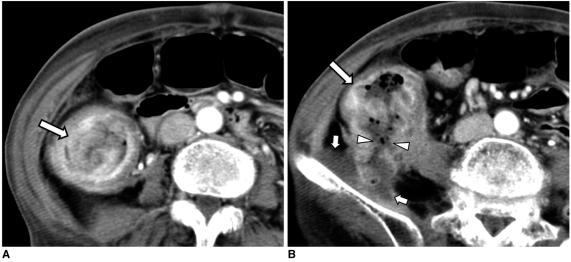

结肠癌相关结肠并发症的 CT 表现

CT findings of colonic complications associated with colon cancer.

A broad spectrum of colonic complications can occur in patients with colon cancer. Clinically, some of these complications can obscure the presence of underlying malignancies in the colon and these complications may require emergency surgical management. The complications of the colon that can be associated with colon cancer include obstruction, perforation, abscess formation, acute appendicitis, ischemic colitis and intussusception. Although the majority of these complications only rarely occur, familiarity with the various manifestations of colon cancer complications will facilitate making an accurate diagnosis and administering prompt management in these situations. The purpose of this pictorial essay is to review the CT appearance of the colonic complications associated with colon cancer.

结直肠癌患者可能会出现广泛的结肠并发症。临床上,这些并发症中的一些可能会掩盖结肠中潜在的恶性肿瘤,这些并发症可能需要紧急手术治疗。可能与结直肠癌相关的结肠并发症包括梗阻、穿孔、脓肿形成、急性阑尾炎、缺血性结肠炎和肠套叠。虽然这些并发症大多数很少见,但熟悉结直肠癌并发症的各种表现形式将有助于在这些情况下做出准确的诊断并进行及时的治疗。本文旨在通过 CT 影像回顾结直肠癌相关结肠并发症的表现。